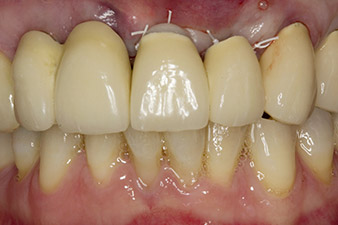

Alla prima visita, il paziente si presentava con ricostruzione su denti 21, 22 e 23 eseguita mediante corone splintate, ormai 19 anni prima, fissate agli impianti con attacchi in corrispondenza delle posizioni 12/11 (cfr. Fig. 2).

Dopo la prima guarigione, i tessuti molli sono stati sagomati con un ponte rivestito nella porzione basale. Due mesi dopo, il sito è stato esposto con una leggera incisione sula cresta palatoalveolare (Fig. 2). Si è visto che le dimensioni dell'osso alveolare erano sufficienti in corrispondenza della posizione 22. Le figure 2 e 4 mostrano la preparazione della sede di impianto, l'avvitamento e l'impianto utilizzando Implantmed.